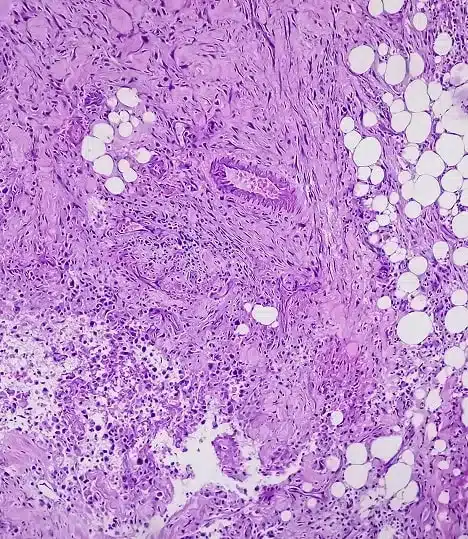

Soy el Dr. Gonzalo Ziegler y me dedico a brindar tratamientos quirúrgicos oncológicos personalizados en piel y mama.

Especialidades quirúrgicas en piel y mama

Cuento con una formación especializada en cirugía oncológica de piel y mama. Cada procedimiento que realizo está enfocado en brindar diagnósticos precisos y tratamientos seguros, adaptados a la necesidad de cada paciente para lograr resultados reales y duraderos.

Soy cirujano oncólogo en Lima con más de una década de experiencia en el diagnóstico y tratamiento de cáncer de mama, melanoma y otras enfermedades oncológicas de la piel. Me especializo en intervenciones quirúrgicas precisas y en el acompañamiento integral de cada paciente, brindando atención en la Clínica Ziegler, una institución comprometida con la salud y el bienestar.

Mi enfoque combina el uso de tecnología médica de última generación, atención cercana y un compromiso constante con la actualización científica. Si estás buscando un mastólogo en Lima o un especialista en tumores de piel, puedo ayudarte a tomar decisiones informadas y seguras para tu tratamiento.